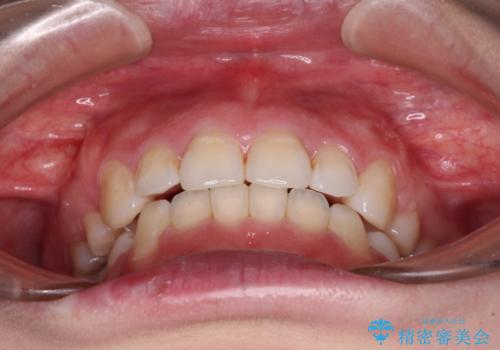

元々上下正中の位置はずれていましたが、治療中によりズレが大きくなったので、元の位置に戻すため治療期間を余計に要しました。

横顔の印象が大きく改善され、患者様には大変満足していただきました。